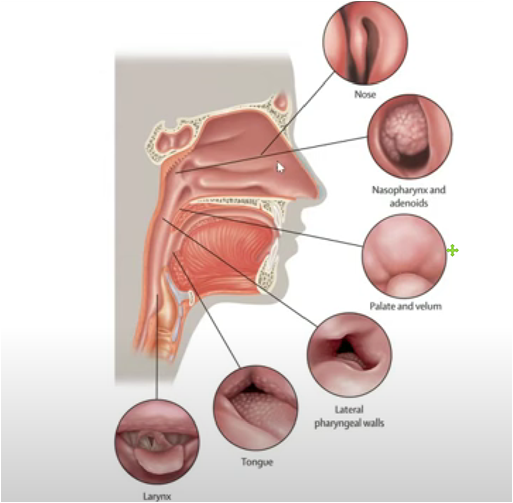

3. Why are respiratory obstruction, allergies and occlusal abnormalities comorbid

According to statistics, OSA is very prevalent, affecting about 34% of men and 17% of women aged 30-70 years. Due to the inconvenience of the use of positive pressure respirators, the effectiveness and convenience of oral devices can popularize the treatment of OSA. As a result, the C4 airway correction system has a large market to be developed. According to the "Overview of China's Oral Medical Service Market", in 2019, there were 885 dental specialties and about 7,000 dental departments in China(Including 6,287 secondary and tertiary general hospitals, 74 tertiary integrated traditional Chinese and Western medicine hospitals, 450 beauty hospitals, and 141 children's hospitals); National Medical Institution Inquiry System of the National Health Commission, As of December 24, 2020, there are 71,397 oral (dental) clinics nationwide. These hospitals or clinics will be the base for the promotion of the C4 airway correction system.

The market positioning of respiratory orthodontic systems is mainly aimed at those patients with snoring and obstructive sleep apnea (OSA), This is especially true in people who have difficulty or are unable to use positive pressure respirators. The advent of such devices offers an alternative that is more suitable for them, aimed at improving their breathing problems and sleep quality.

In addition, the system's custom design, including C4 braces, palate slow bone expansion and Angel therapy, allows it to more precisely meet the needs of patients and provide more effective and comfortable treatment options, which is also a major advantage in the market.

According to some reports, snoring and sleep apnea syndrome (OSA) are common problems for a large portion of the population, and these problems are likely to worsen as obesity rates increase. Snoring and sleep apnea are not just sleep problems, they are also linked to health problems such as heart disease, stroke, diabetes, and more. However, most of those affected are not diagnosed or treated.